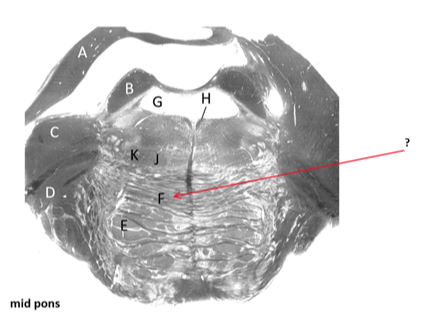

Name this and state its function.

Pathway.?

Pyramidal tracts.

Descending Pathway: Motor fibres, carrying information from Cortex—>brain and spine–> lower motor neurons.